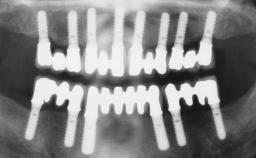

A 61-year-old male patient with a failing fixed maxillary rehabilitation and a fixed mandibular rehabilitation requested a new fixed maxillary rehabilitation. The patient was wearing a temporary metal-reinforced maxillary bridge inserted two years before the consultation. He reported that his previous dentist did not want to insert a definitive framework because he considered the residual teeth to have a negative prognosis. The patient reported a history of recurrent caries and endodontic complications as the main reason for the previous extractions. The anamnesis was negative for periodontal disease and bruxism. The patient’s chief compliant was the mobility of his maxillary prosthesis, which needed to be re-cemented frequently, and discomfort during chewing.Moreover, the patient was not satisfied with the esthetic appearance of his maxillary teeth, which he found too long. The patient asked for a stable and comfortable fixed maxillary rehabilitation and firmly rejected any removable solution.